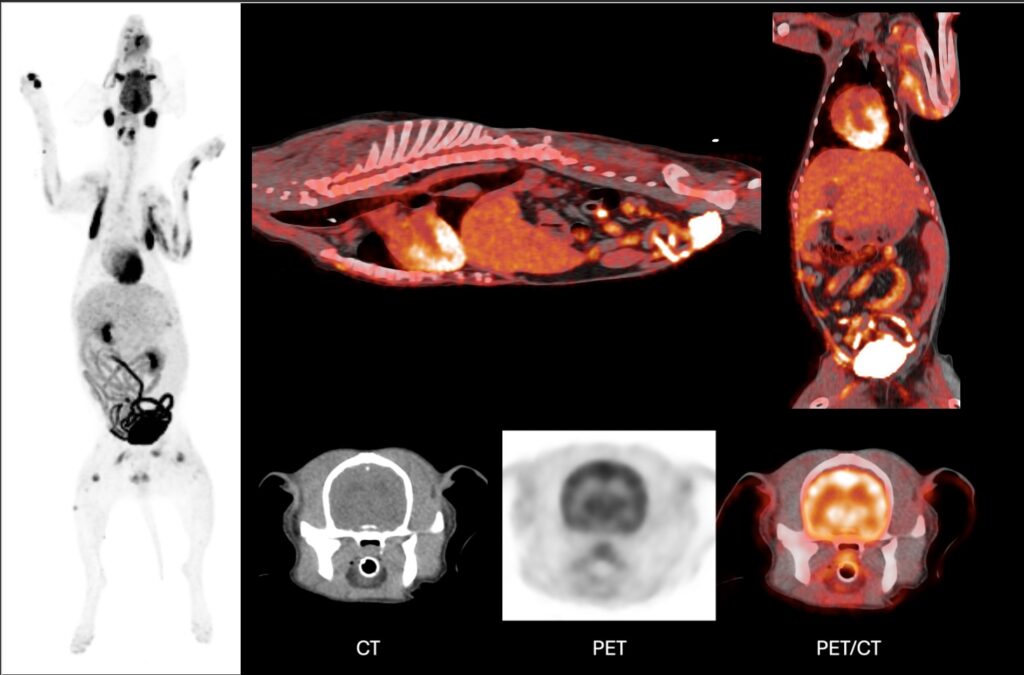

UWVC’s renovated oncology suite quadruples the space available to our clinicians to see cancer patients and doubles the hospital’s space for chemotherapy treatment. It’s also home to PET-CT, an advanced diagnostic tool that is redefining how diseases are diagnosed and treated in animals. Where it occurs: Most commonly causes enlargement of multiple lymph nodes and can occur in almost any part of the body.

PET-CT, which has been used for years in human medicine, is a non-invasive, whole-body scan that can detect disease earlier than traditional imaging. Radiation Therapy